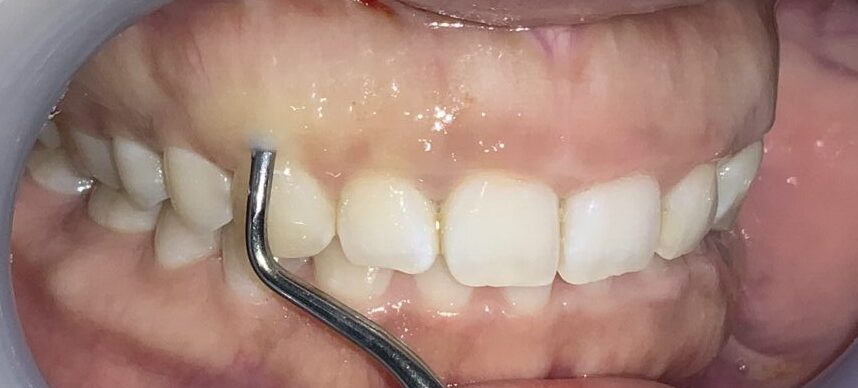

反対側の歯も調べてみます。前歯の形はとても大切ですから、慎重に検査を進めます。

この歯も同じように、たくさんの歯ぐきが、かぶさっています。

隣の歯も同じように検査します。

隣の歯は前歯ほどではないですが、しっかりと歯ぐきが、かぶっています。